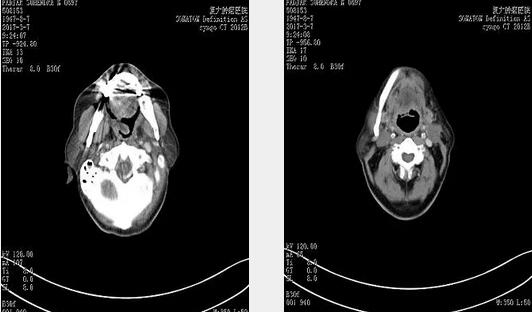

2016年11月5日治疗前CT 显示左侧扁桃体鳞癌,肿瘤侵犯舌根及会厌,口咽腔狭窄。

2017年3月7日2次消融后CT,左侧扁桃体肿瘤明显退缩。

2017年7月4日颈部淋巴结清扫术后CT,原双侧颈部转移性病变,已消失。